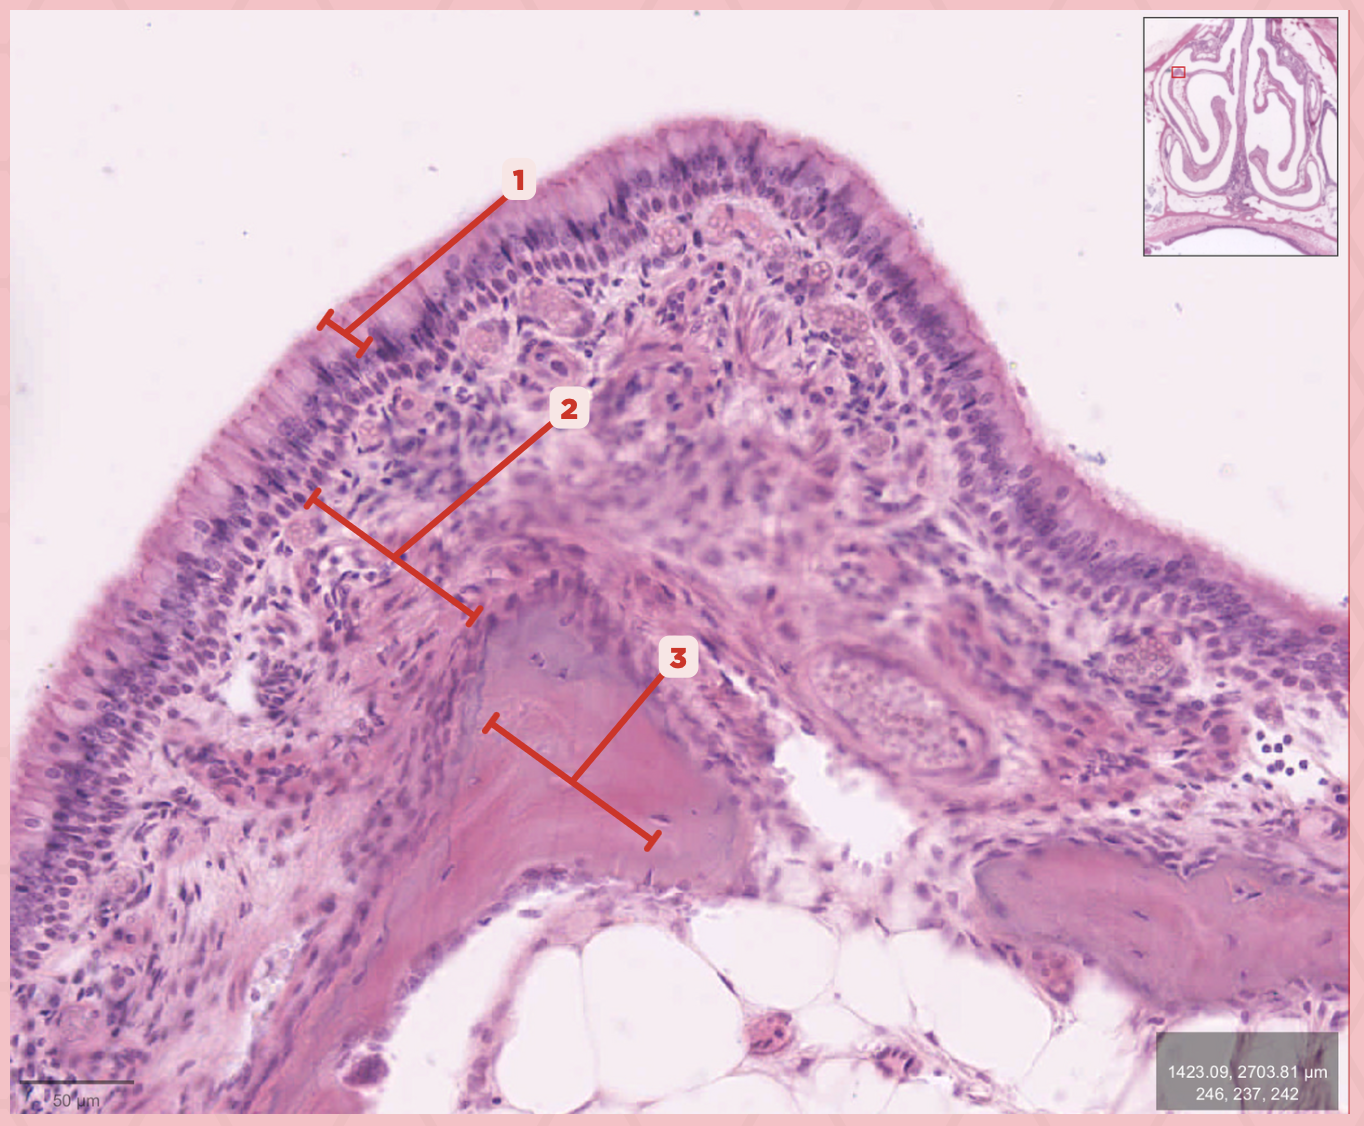

Respiratory Epithelium

Identify the structure labeled as 1.

Lamina Propria

Identify the structure labeled as 2.

Bony spicule

Identify the structure labeled as 3.

Respiratory Epithelium

What epithelium lines this structure?

Ciliated pseudostratified epithelium

What type of epithelium lines this structure?

Respiratory Epithelium

Identify the structure labeled as 1.

Mucosa

Identify the structure labeled as 2.

Bone

Identify the structure labeled as 3.

Keratinized stratified squamous epithelium

What’s the lining epithelium at #3?

No

Are Glands present at #1?

Lamina Propria

Identify the structure labeled as 1.

Adipocytes

Identify the structure labeled as 2.

Keratinized stratified squamous epithelium

Identify the structure labeled as 3.